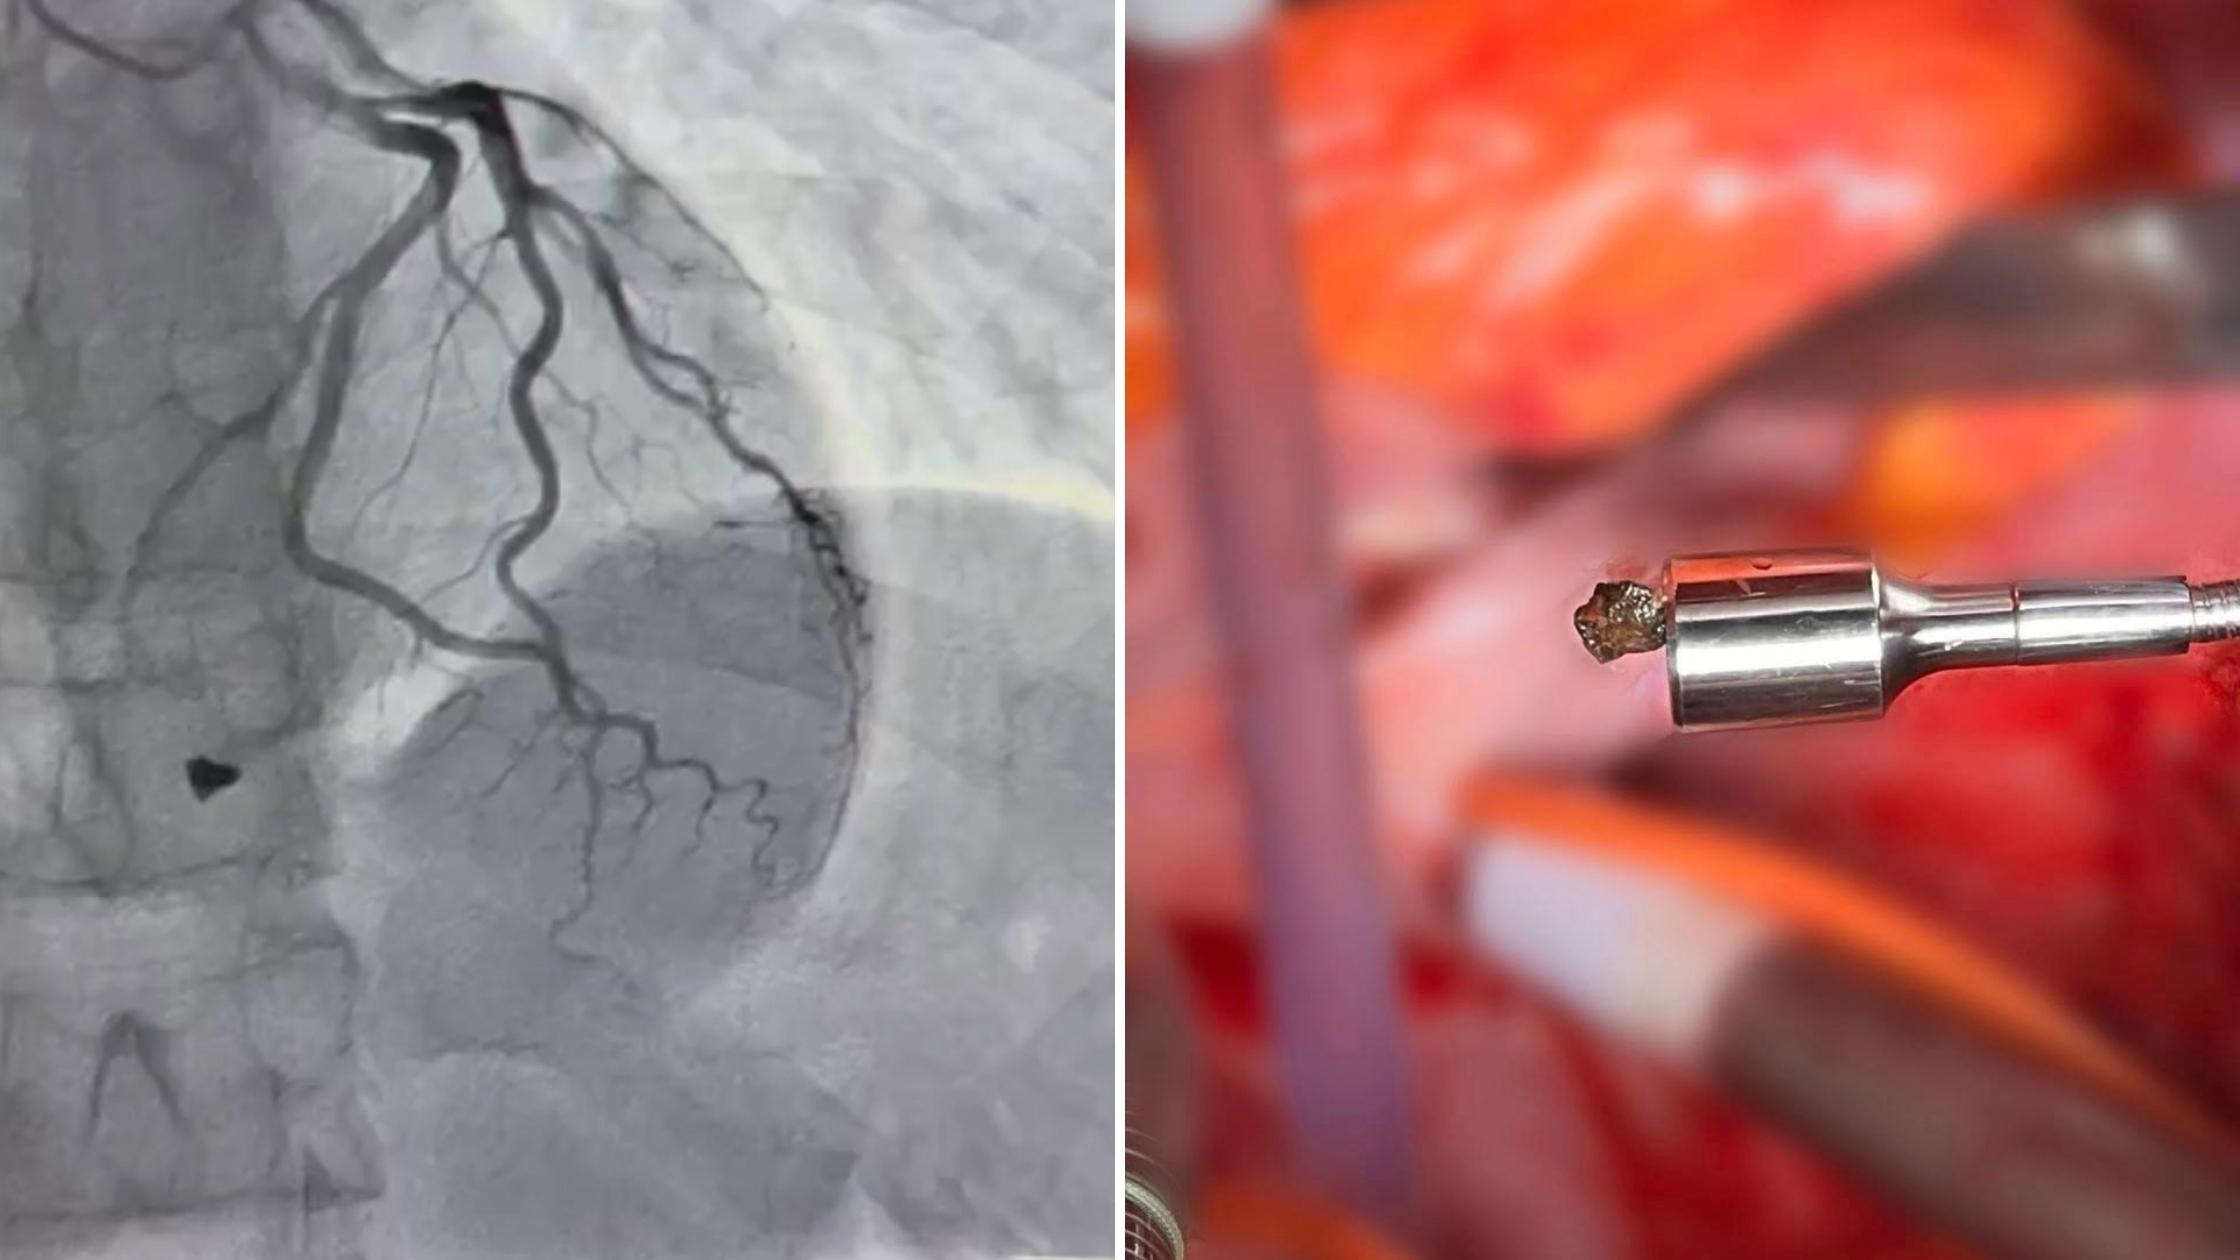

Під час ретельного обстеження пацієнта встановили: металевий уламок локалізувався в зоні клапанного апарату серця з пошкодженням папілярного мʼяза тристулкового клапана. Це не просто травма, а загроза втрати повноцінної та компетентної роботи клапана серця, - йдеться у повідомленні.

Після детального аналізу анатомії травми кардіохірургічна команда лікарні видалила вогнепальний уламок та здійснила пластику тристулкового клапана, що дозволило відновити його функцію і забезпечити стабільну роботу серця.